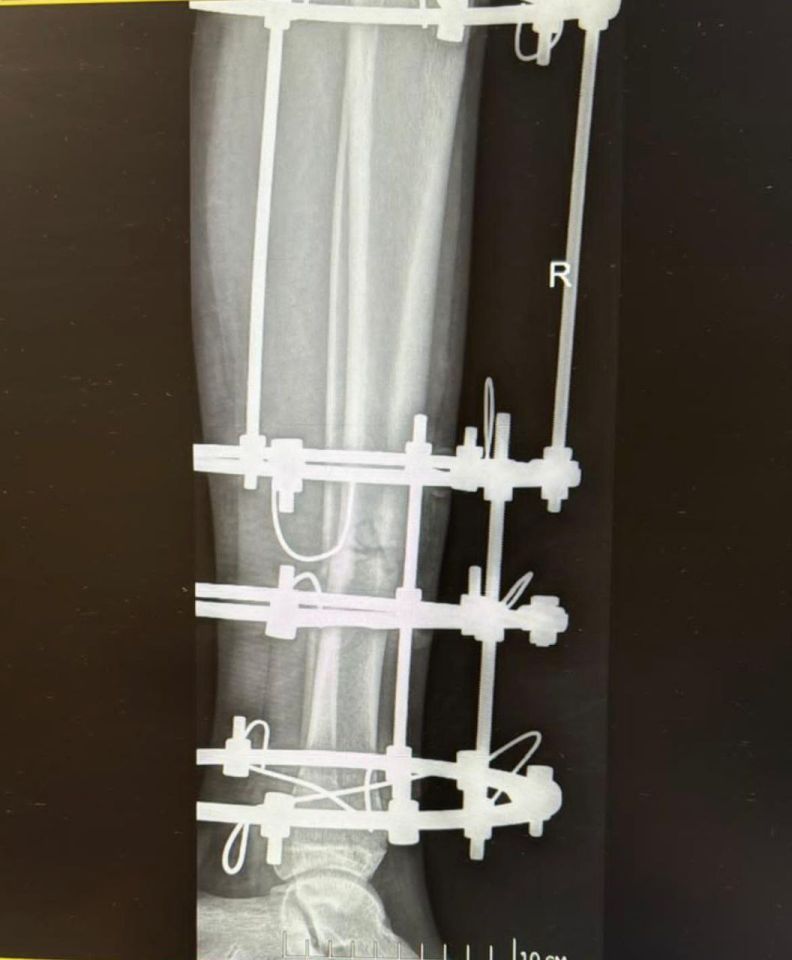

Прибывшая на место бригада скорой помощи экстренно госпитализировала юношу в горбольницу Владивостока. Диагноз врачей шокировал: открытый перелом обеих берцовых костей левой ноги.

«Сначала пациент находился на скелетном вытяжении, чтобы привести повреждённые костные отломки в правильное анатомическое положение. На этапе хирургического вмешательства врачи выполнили репозицию костных отломков с наложением аппарата Илизарова, что позволит обеспечить правильное сращение костей и минимизировать риск осложнений. Полный процесс восстановления займёт от 6 до 8 месяцев», - сообщила врач-травматолог-ортопед.